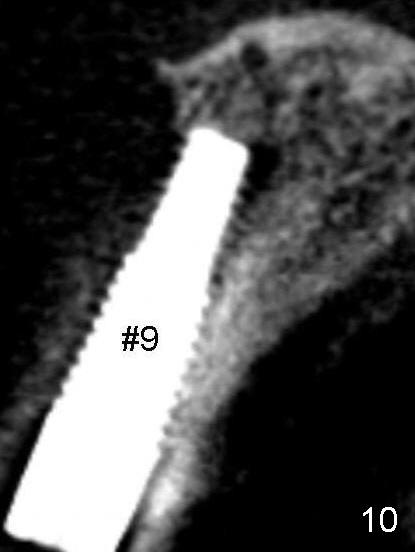

Tooth #8 has an expanding radiolucency (Fig.9 * as compared to Fig.10).  Antibiotic is not going to fix this. Apico surgery will destroy the nice buccal bone (Fig.9 >). I have seen this before, The best choice is to remove the implant with a little curettage at the apex area only. Put a hemostatic gauze, absolutely no bone graft needed. Let it heal for 4 to 6 month. Then implant again.